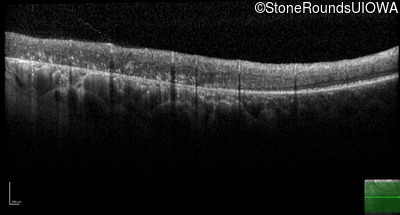

Optical Coherence Tomography - Right - 20/25 -1

Exemplar / OCT Stack